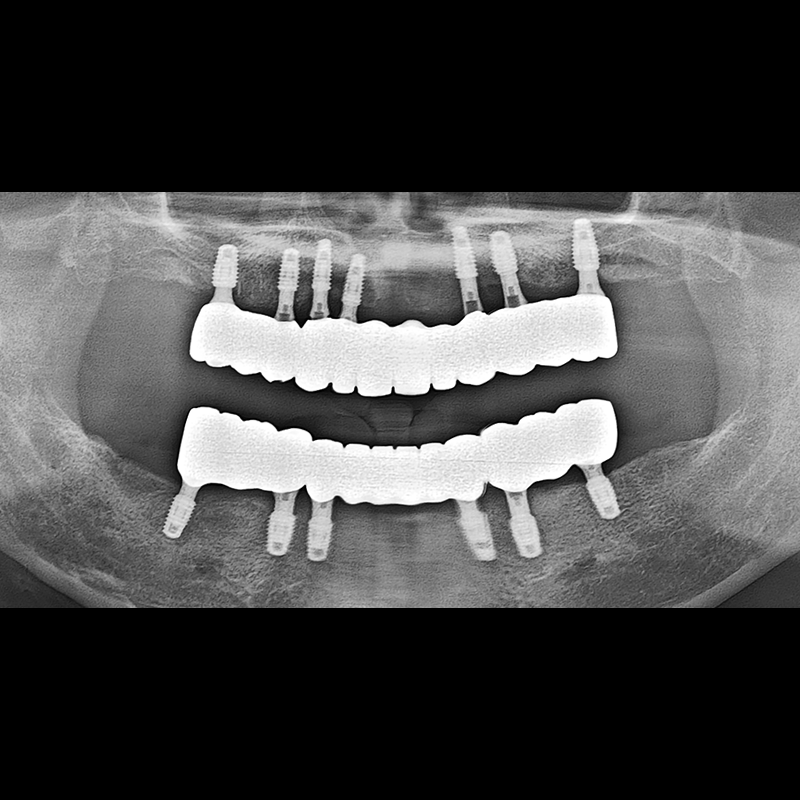

IMPLANT

BEFORE AFTER

インプラント手術事例 2025.05.30

欠損した歯の部分と、生かしにくい歯の位置にインプラントを植立しました。